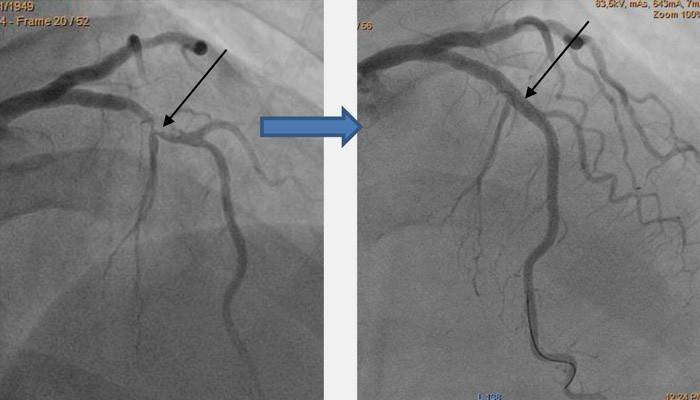

O implante de stent das artérias coronárias só pode ser feito após o diagnóstico completo, incluindo angiografia - exame com raio X e contraste do sistema cardiovascular. Isso ajuda a determinar a presença de estreitamento nos vasos, sua localização, extensão e outras nuances. Com base nos dados, o médico decide se o implante de stent é aceitável para o paciente e seleciona o tipo apropriado de tubo.

O implante de stent ocorre sob condições estéreis na sala de cirurgia, utilizando um anestésico local. A instalação de stents é feita sob o controle da fluoroscopia. Para obter acesso aos vasos danificados, o médico perfura uma grande artéria.Um pequeno tubo (introdutor) é inserido através do orifício. É necessário introduzir outros instrumentos na artéria. Um cateter flexível é levado através do introdutor até a boca da artéria afetada. Através dele, um stent é entregue diretamente no local de estreitamento do vaso.

O especialista coloca o tubo de forma que, após a abertura, esteja localizado o melhor possível. Em seguida, o balão do stent é preenchido com contraste, o que leva ao seu inchaço. Sob pressão, o tubo se endireita. Se o stent estiver posicionado corretamente, o médico retira os instrumentos e ataduras do local da punção. O implante de stent em média leva de 30 a 60 minutos, mas é estendido se vários tubos forem necessários de uma só vez.